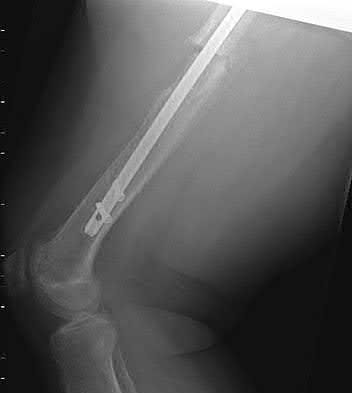

This patient has sustained a low-velocity gunshot to the right femoral diaphysis. The next best step in treatment would be insertion of a reamed antegrade or retrograde intramedullary nail. During surgery, the gunshot wound could be closed primarily if it was considered clean, or allowed to heal by secondary intention if it was there was any concern.

Low-velocity gunshot wounds are typically treated as closed fractures, since the risk of osteomyelitis is very low. These are typically bullets from handguns that travel 600 meters per second). The timing and direction (e.g. antegrade or retrograde) of nail insertion has not shown to

affect outcomes.

Figure A shows an AP radiograph of the right femur. There is a gunshot fracture in the proximal femoral shaft with retained bullet fragments. The leg has been placed in temporary traction.